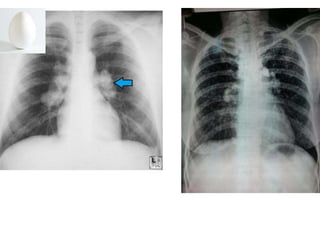

Chest X-ray of Uncomplicated

Silicosis

 Enlargement of hilar nodes may precede

parenchymal disease

 Uncomplicated silicosis has small round

opacities

 Egg-shell calcification of the hilum is

suggestive of silicosis

 Occasional can calcify

morphology

Chest X-ray ofUncomplicated Silicosis  Enlargement of hilar nodes may precede parenchymal disease  Uncomplicated silicosis has small round opacities  Egg-shell calcification of the hilum is suggestive of silicosis  Occasional can calcify

Pleural Disease Associated with

Asbestosis

 Pleural Plaques

 Pleural Thickening

 Pleural Effusion

 Mesothelioma

Pleural Plaques

 Smooth white raised lesions located on the posterolateral

aspect of the parietal pleura or diaphragm

 Plaques vary in size & shape

 Asymptomatic in pts without parenchymal disease

 Presence of plaques is associated with likelihood of

developing parenchymal disease

 Rarely seen before 20yrs after exposure

Pleural Disease Associatedwith Asbestosis  Pleural Plaques  Pleural Thickening  Pleural Effusion  Mesothelioma

Pleural Plaques  Smoothwhite raised lesions located on the posterolateral aspect of the parietal pleura or diaphragm  Plaques vary in size & shape  Asymptomatic in pts without parenchymal disease  Presence of plaques is associated with likelihood of developing parenchymal disease  Rarely seen before 20yrs after exposure